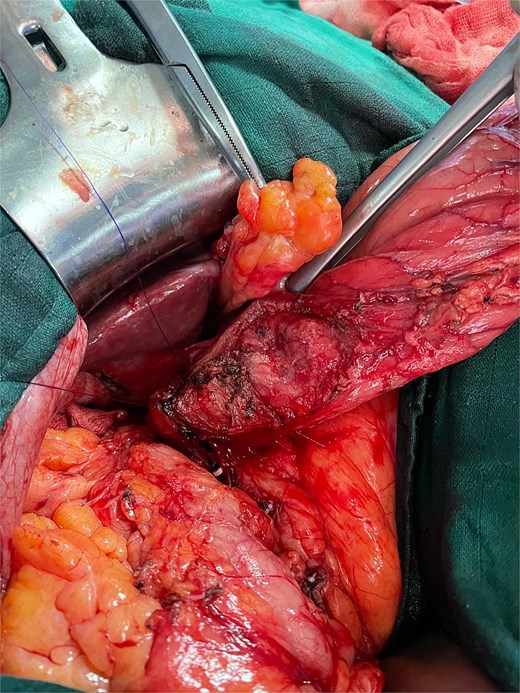

Meticulous dissection allowed liberation of the gallbladder and separation of the pseudocystic gastric formation, with aspiration of purulent content from both the gallbladder and the fistulous tract. Antegrade cholecystectomy was performed with clipping and division of the cystic artery and duct. The fistulous tract was carefully dissected, and partial resection of the affected gastric wall was completed (Fig. 4), followed by closure with 3–0 PDS suture, preserving the gastric mucosa integrity (Fig. 5).

Intraoperative image after resection of the gallbladder and the subserosal gastric cyst.